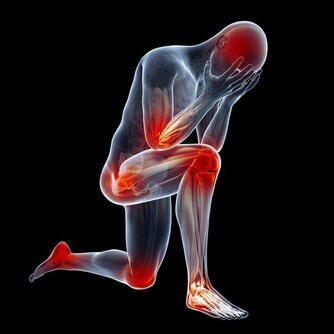

缺乏維生素,身體有什麼表現?

維生素B存在很多種,一般統稱為維生素B族,這可物質能夠讓人體的骨骼更加強壯,還能幫助促進人體新陳代謝。而當人體缺乏維生素B時,就可能引發多種疾病。

其中,缺乏維生素B1,容易引起消化不良、厭食、大便乾燥等症狀,嚴重的還會導致嘔吐、四肢浮腫等;

而缺乏維生素B6時,人的口唇、舌頭可能會有腫痛感,手指、腳趾還可能出現酥麻的刺痛感。